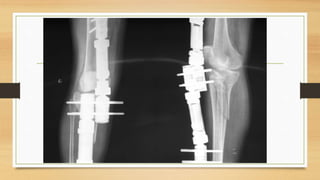

Que operar primero, y cuanto tiempo esperar?

•Fractura

• Ligamentos cruzados?

• Ligamentos colaterales?

• Meniscos ?

Existe poca evidencia y reportes.

Si se identifica una fractura, trate de forma quirúrgica o no quirúrgica, según corresponda, y vuelva a

evaluar la estabilidad de los ligamentos 6 semanas después de la lesión. Según lo recomendado por

Stannard : la fractura debe tratarse primero, y las lesiones ACL y PCL pueden tratarse después de la

curación de la fractura. Si se observan signos radiológicos y clínicos continuos de inestabilidad

sintomaticos se procede a la reparación de los LCM y LCL, Si hay signos radiográficos de inestabilidad

pero el paciente es asintomático por inestabilidad, considere el manejo no operatorio de las lesiones.

Recomienda la reparación ligamentaria en pacientes menores de 50 años, 50-60 si son sontomaticos,

mayores de 60 pobres resultados

Otros sugieren en un solo tiempo

Cuando están asociadas fractura de platillo

tibial y lesión multiligamentaria

_Si hay inestabilidad muy marcada puede realizarse de primera intención

_Se prefiere dar chance para cicatrización de estructuras ligamentarias y una

reevaluación 6 a 8 -12-semanas después